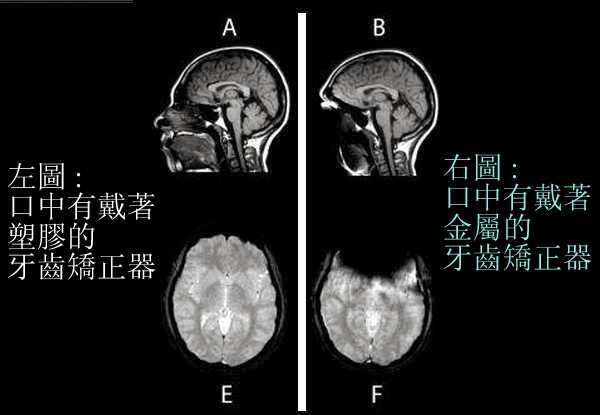

(9)"老闆娘, 我也要來一張!"在台灣的健保, 病況需要時每半年可以免費照一張MRI. 所以只要在頭頂上噴灑一些金屬粉末, 並用髮膠固定. 細小的黑粉末是一定可以讓現場醫事檢驗人員既看不出來也摸不出來, 如此就可瞞過醫院. 去看醫生時就說頭內部很不舒服. 要求要照MRI. 公立醫院通常比較不會輕易讓病人照MRI. 少數私立醫院因為購買MRI機器的成本非常昂貴, 因此比較可能會照MRI, 目的顯然是為了回本.

就這樣, 你幾乎不花一毛錢, 就可以輕易瞞天過海又免費照出並拿到"開頂成聖"的MRI影像圖了. 先讓台灣健保替你付費. 如果你要, 還可在公車火車坦克車上打廣告, 再讓台灣信徒把你當大聖德大法王敬拜供養.